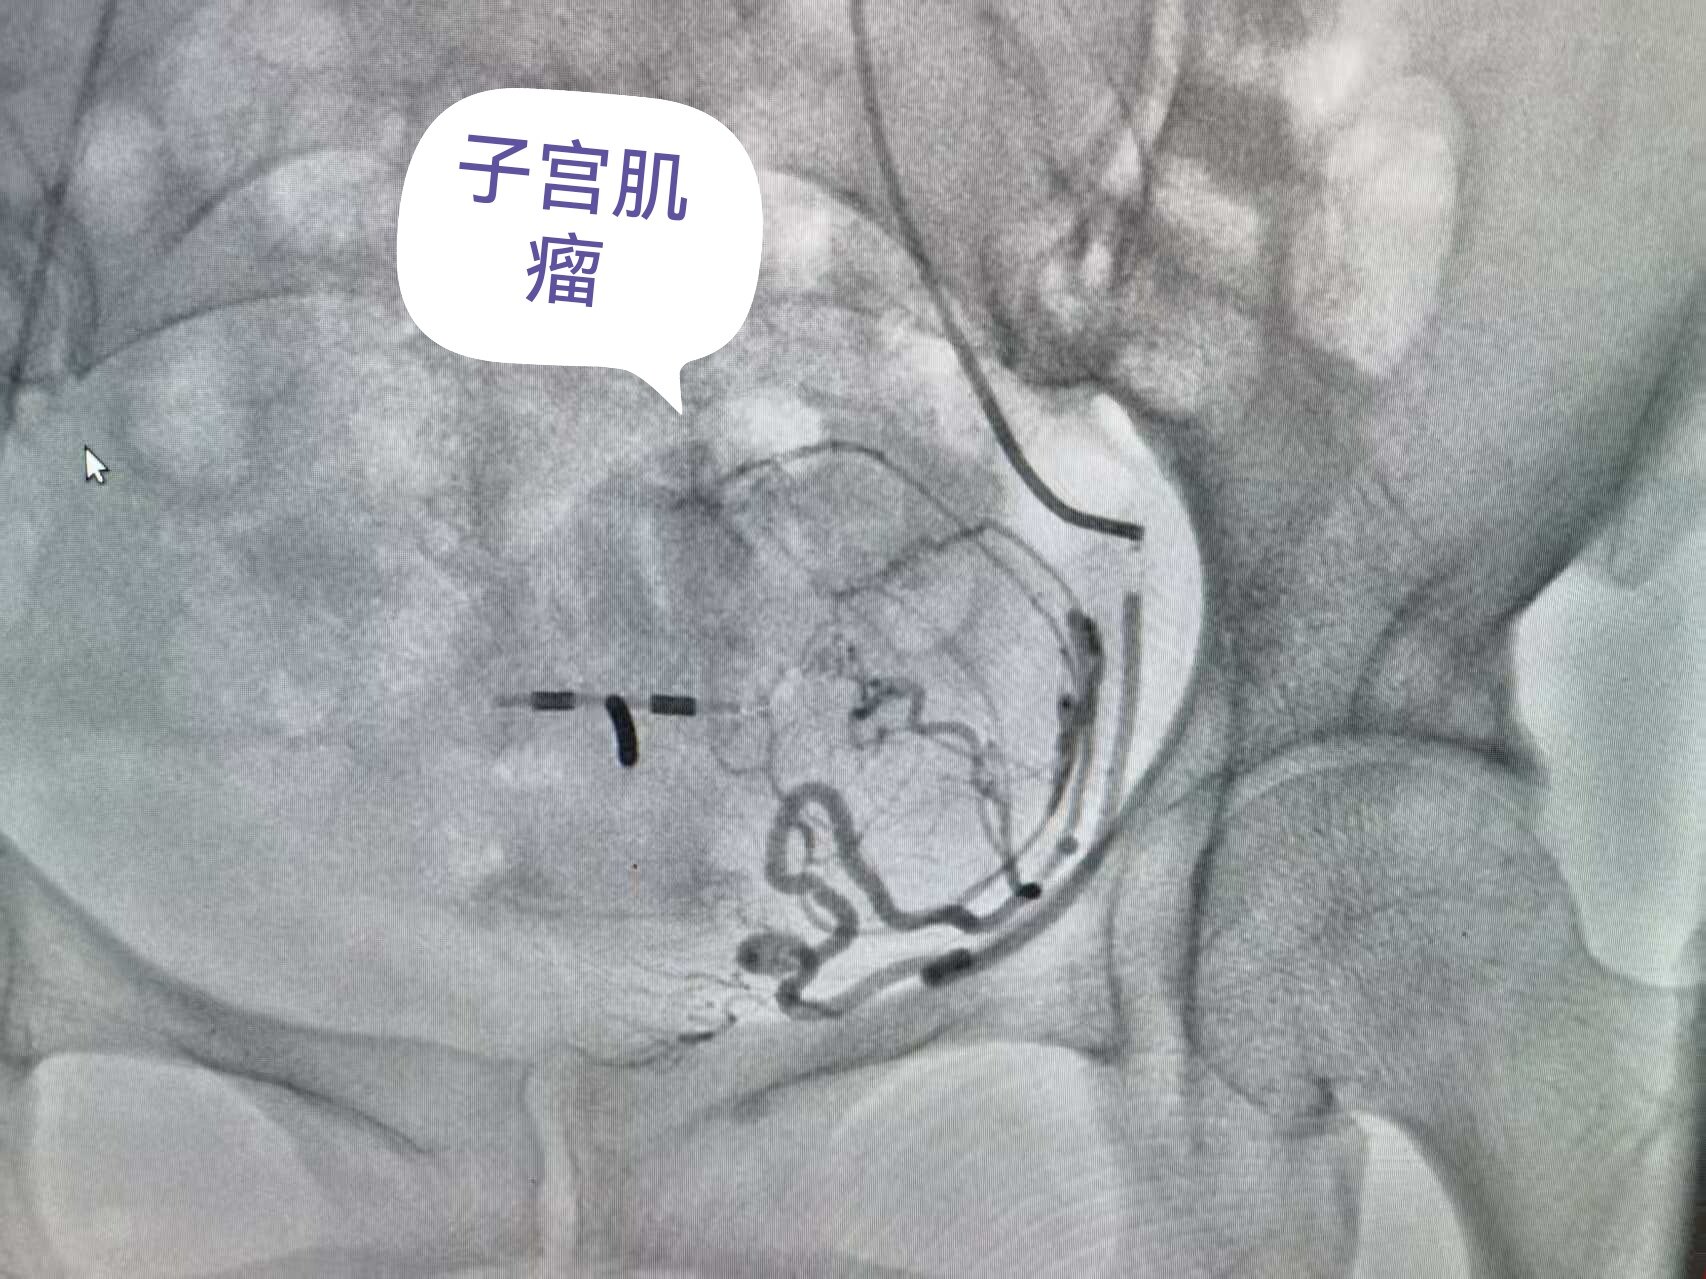

1. 微创穿刺:局麻后,通过大腿根部约2mm的针孔,将导管插入到子宫动脉内(图2),术后仅留一个小针眼。

图2 子宫动脉造影确定子宫肌瘤的位置。